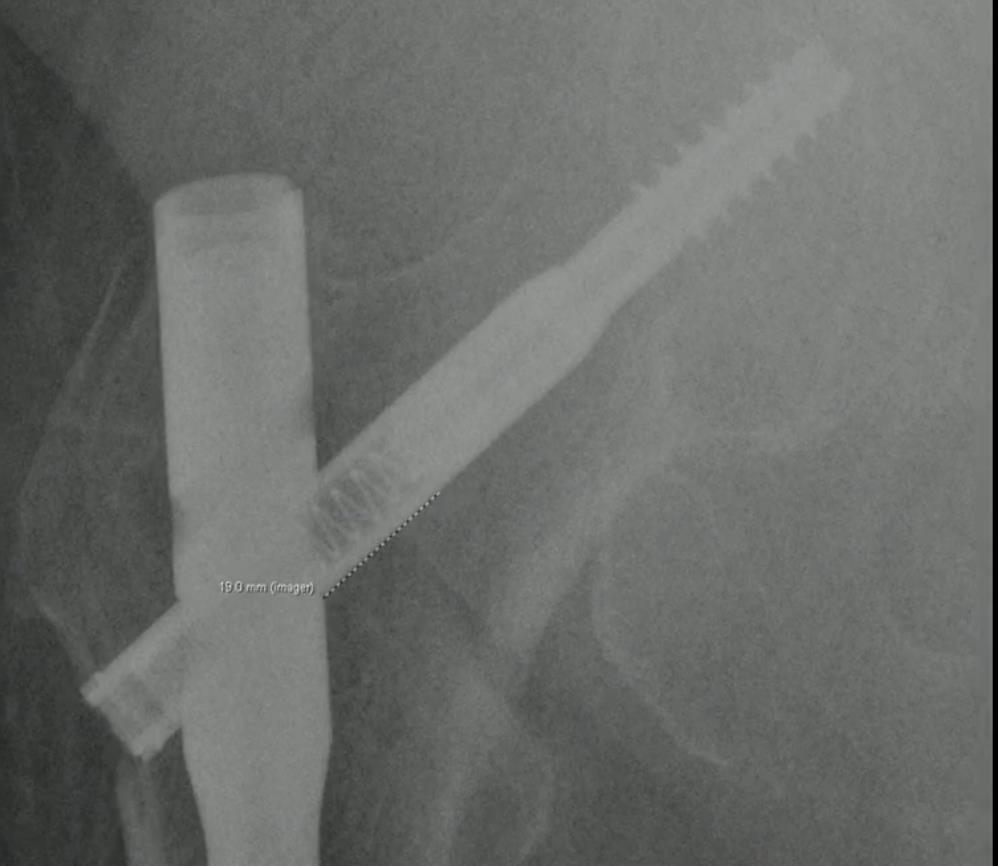

Trochanteric Nail System

• Intramedullary fixation is standard for many unstable pertrochanteric and subtrochanteric fractures. The Arthrex Trochanteric Nail System is a cephalomedullary construct available in short, extended-short (ES), and long configurations, with a telescoping lag screw, optional anti-rotation screw, and an augmentation system for biologic or cement injection through the lag screw tract.

• A 10.5 mm telescoping lag screw is designed to collapse within the screw itself, aiming to allow controlled fracture compression while limiting lateral screw prominence and soft-tissue irritation compared with conventional sliding constructs.

• Lag screw length and reaming depth are determined with a dual-sided lag screw depth gauge

• One side measures reaming depth from the pin guide to the wire tip.

• The other side accounts for the position of the internal locking ring when the screw is advanced to the pin tip.

• A legacy depth gauge is also available but requires manual subtraction to account for subchondral clearance and planned compression.

• The adjustable stop on the cannulated lag screw drill is set to 5–10 mm shorter than the measured depth so the drill tip remains short of the guidewire tip.

• The 10.5 mm telescoping or solid locking lag screw is coupled to the inserter via a capturing rod and a castle-type interface, with alignment marks confirming proper engagement.

• The lag screw is advanced over the guide pin until a laser mark on the inserter aligns with the sheath, indicating the screw has passed fully through the sheath.

• If intraoperative compression is planned, the screw should be countersunk appropriately to provide room for sliding before the internal locking ring engages.

• A compression sleeve on the inserter is advanced toward the targeting arm and rotated clockwise to apply fracture compression through the telescoping screw.

• If the screw has been advanced too far laterally to lock, the mechanism free-spins and displays a red line in the handle window, signaling that additional screw advancement into the head is required before compression can be completed.

• Once the desired compression is achieved, the integrated locking knob is engaged.

• Holding the main handle stationary, the locking handle is turned clockwise until a torque limiter clicks, indicating that the telescoping or solid lag screw is locked to the nail without a separate set screw.